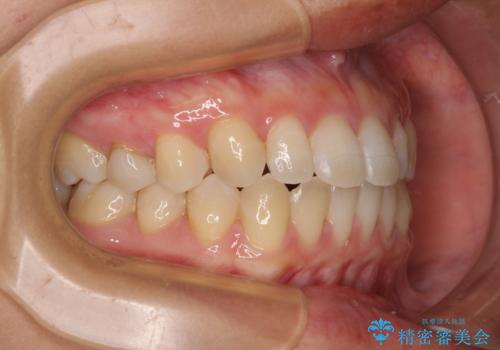

隙間だらけの歯列 インビザラインで改善

- 前歯の上下スペースと前歯の隙間を気にして来院された患者様です。

飲み込みや話をするときに舌を突出させる癖が強くあり、それが原因でスペースが空いていました。

舌癖を改善するためのトレーニングを行いながら、インビザラインにより上下の前歯の隙間を閉じていくこととしました。